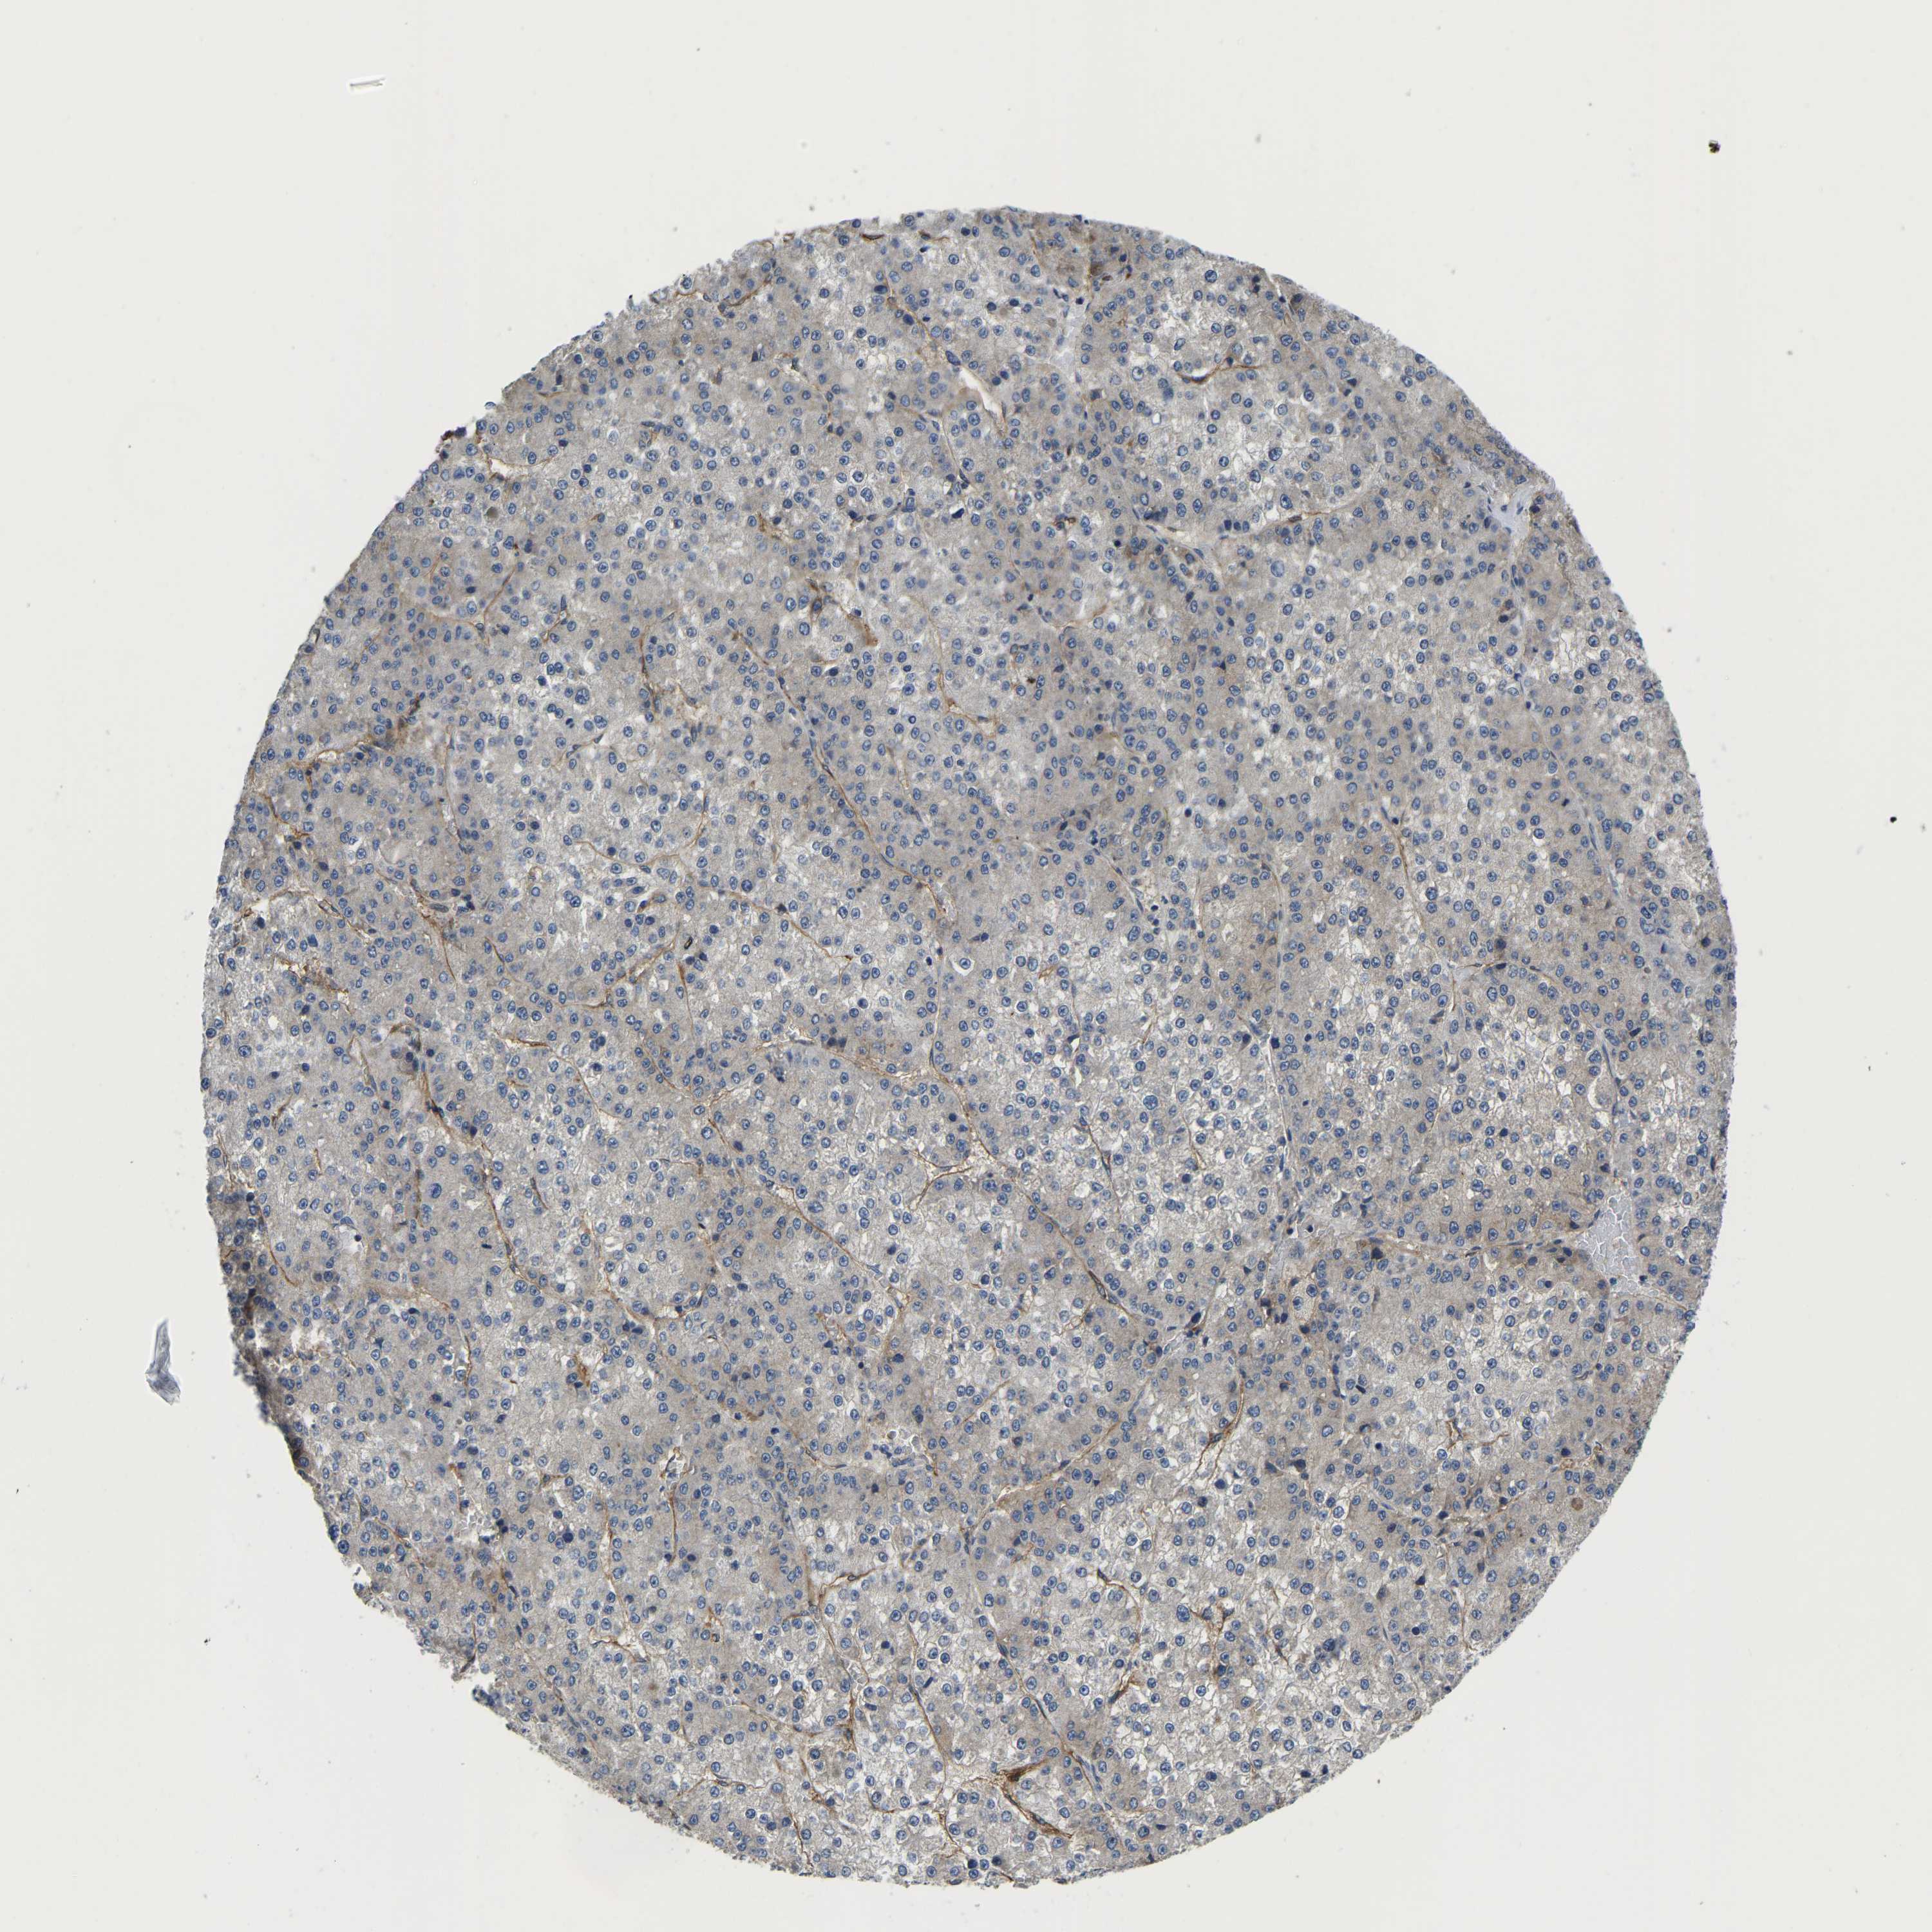

LIVER CANCER - Protein expressioni

A mouse-over function shows sample information and annotation data. Click on an image to view it in a full screen mode. Samples can be filtered based on level of antibody staining by selecting one or several of the following categories: high, medium, low and not detected. The assay and annotation is described here.

Note that samples used for immunohistochemistry by the Human Protein Atlas do not correspond to samples in the TCGA dataset.

Antibody stainingi

Antibody staining in the annotated cell types in the current human tissue is reported as not detected, low, medium, or high, based on conventional immunohistochemistry profiling in selected tissues. This score is based on the combination of the staining intensity and fraction of stained cells.

Each image is clickable and will lead to virtual microscopy that enables deeper exploration of all samples and also displays staining intensity scores, fraction scores and subcellular localization as well as patient and tissue information for each sample.

Antibody HPA060991

Antibody HPA063556

Antibody CAB017690

Staining

High

Medium

Low

Not detected

Intensity

Strong

Moderate

Weak

Negative

Quantity

>75%

75%-25%

<25%

None

Location

Nuclear

Cytoplasmic/membranous

Cytoplasmic/membranous,nuclear

Carcinoma, Hepatocellular, NOS

Cholangiocarcinoma